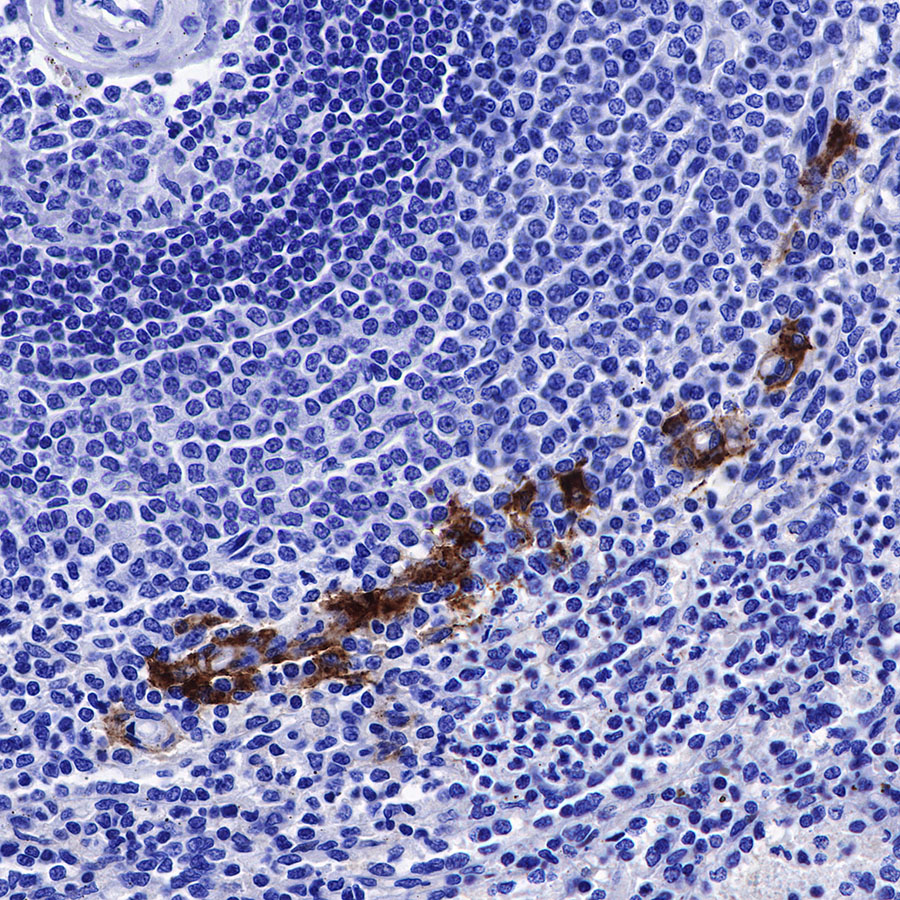

IHC shows positive staining in paraffin-embedded human spleen. Anti-CD169 antibody was used at 1/250 dilution, followed by a HRP Polymer for Mouse & Rabbit IgG (ready to use). Counterstained with hematoxylin. Heat mediated antigen retrieval with Tris/EDTA buffer pH9.0 was performed before commencing with IHC staining protocol.

Picture